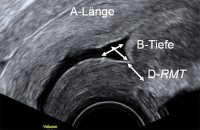

Tipps und Tricks im Gyn-Ultraschall: Die Sectionarbe am nichtschwangeren Uterus und in der Frühschwangerschaft

Journal für Gynäkologische Endokrinologie 2014; 8 (2) (Ausgabe für Österreich): 22-24 Journal für Gynäkologische Endokrinologie 2014; 8 (2) (Ausgabe für Schweiz): 24-26 Volltext (PDF) Abbildungen